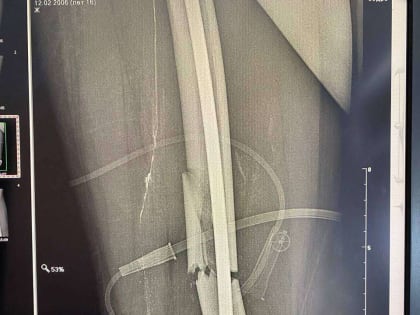

В Оренбурге врачи ОДКБ и горбольницы №4 провели сложную операцию на бедренной кости

Врачи ОДКБ совместно с хирургами Городской больницы №4 сделали операцию подростку, у которого была сломана левая бедренная кость со смещением отломков.

Оренбургские хирурги провели уникальную операцию подростку

В Оренбурге врачи ОДКБ и четвертой городской больницы провели уникальную операцию на ноге подростка.